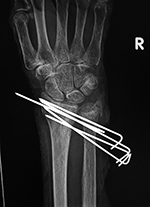

Left ankle syndesmotic screw fracturing |

22 year-old man with syndesmotic screw placement for medial avulsive ankle injury. The screws fractured and loosened and were later removed. |